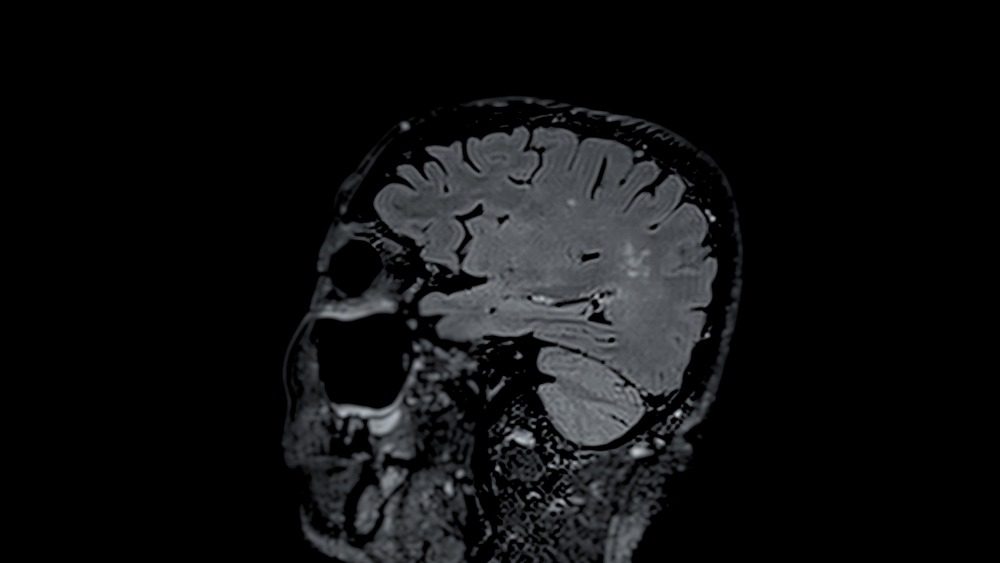

Crash Head Injury Prognosis Calculator . crash is a tool to estimate mortality and disability in adult tbi patients with gcs of 14 or less. based on the corticosteroid randomisation after significant head injury (crash) trial database, a prognosis calculator has been. these prognostic models may be used as an aid to estimate mortality at 14 days and death and severe disability at six months. It uses two sets of models based. traumatic brain injury (tbi) is a leading cause of death and disability. Establishing a reliable prognosis early after injury is notoriously. road traffic crashes were a more common cause of traumatic brain injury. the medical research council (mrc) crash (corticosteroid randomisation after significant head injury) trial is the.

these prognostic models may be used as an aid to estimate mortality at 14 days and death and severe disability at six months. traumatic brain injury (tbi) is a leading cause of death and disability. crash is a tool to estimate mortality and disability in adult tbi patients with gcs of 14 or less. the medical research council (mrc) crash (corticosteroid randomisation after significant head injury) trial is the. It uses two sets of models based. based on the corticosteroid randomisation after significant head injury (crash) trial database, a prognosis calculator has been. road traffic crashes were a more common cause of traumatic brain injury. Establishing a reliable prognosis early after injury is notoriously.